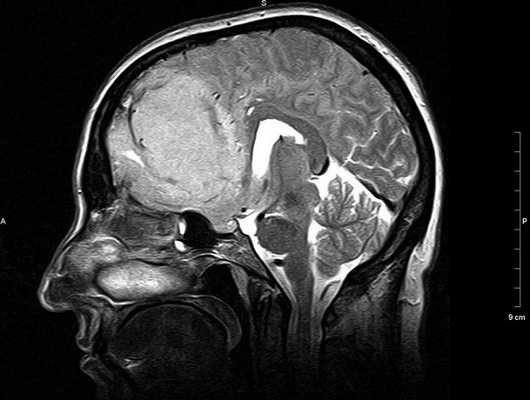

МРТ головного мозга. Сагиттальная Т1-зависимая МРТ. Липома и агенезия мозолистого тела.

Липома представляет собой жировые клетки под паутинной оболочкой мозга. Липомы формируются в период эмриогенеза в связи с неправильным расположением зачаточных жировых клеток в области мозговых оболочек. остатков примитивной эмбриональной оболочки. Липома может рассматриваться как аномалия развития и как доброкачественные опухоли из группы мезенхимальных опухолей (оболочечные неменинготелиальные). Частота липом составляет не более 1% от кистоподобных образований и еще меньше от опухолей мозга. Липомы чаще всего располагаются по средней линии: в межполушарной щели, в мозолистом теле, воронке гипофиза и гипоталамусе , реже вокруг червя мозжечка и пластины четверохолмия. Однако встречаются внеосевые липомы, например, в мосто-мозжечковом углу. Липомы головного мозга, в отличие от позвоночника, изредка сочетаются с другими аномалиями развития. Липома мозолистого тела часто видна в месте с недоразвитием его задней трети и изредка с переходом жировой ткани на сосудистое сплетение желудочков. При МРТ головного мозга имеет типичные черты: она может иметь любую форму, но резко очерчена, без перифокального отека и не дает масс-эффекта, не разрушает соседние структуры. Внутри липома чаще изредка неоднородная из-за участков кальция и сосудов. Главный признак липомы - она имеет интенсивности сигнала жировой ткани при МРТ, то есть выраженно гиперинтенсивная на Т1-зависимых МРТ головного мозга и немного менее интенсивная по отношению к ликвору на Т2-зависимых МРТ головного мозга. В отличие от близких по виду эпидермоидных и тератоидных кист, МРТ головного мозга с подавлением жира показывает полное исчезновение жирового сигнала.